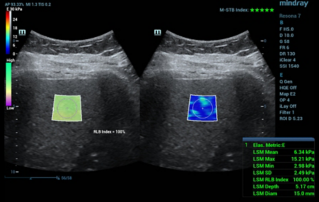

Female pelvic floor anatomy, which developed since the early 20th century, has had a variety of theories, including integral theory, three levels of vaginal support theory, "hammock hypothesis", and three-chamber system. Supporting structures such as pelvic floor muscles, fascia and ligament play an important role in maintaining the normal function of pelvic floor, among which levator ani muscle group is one of the most important supporting structures.